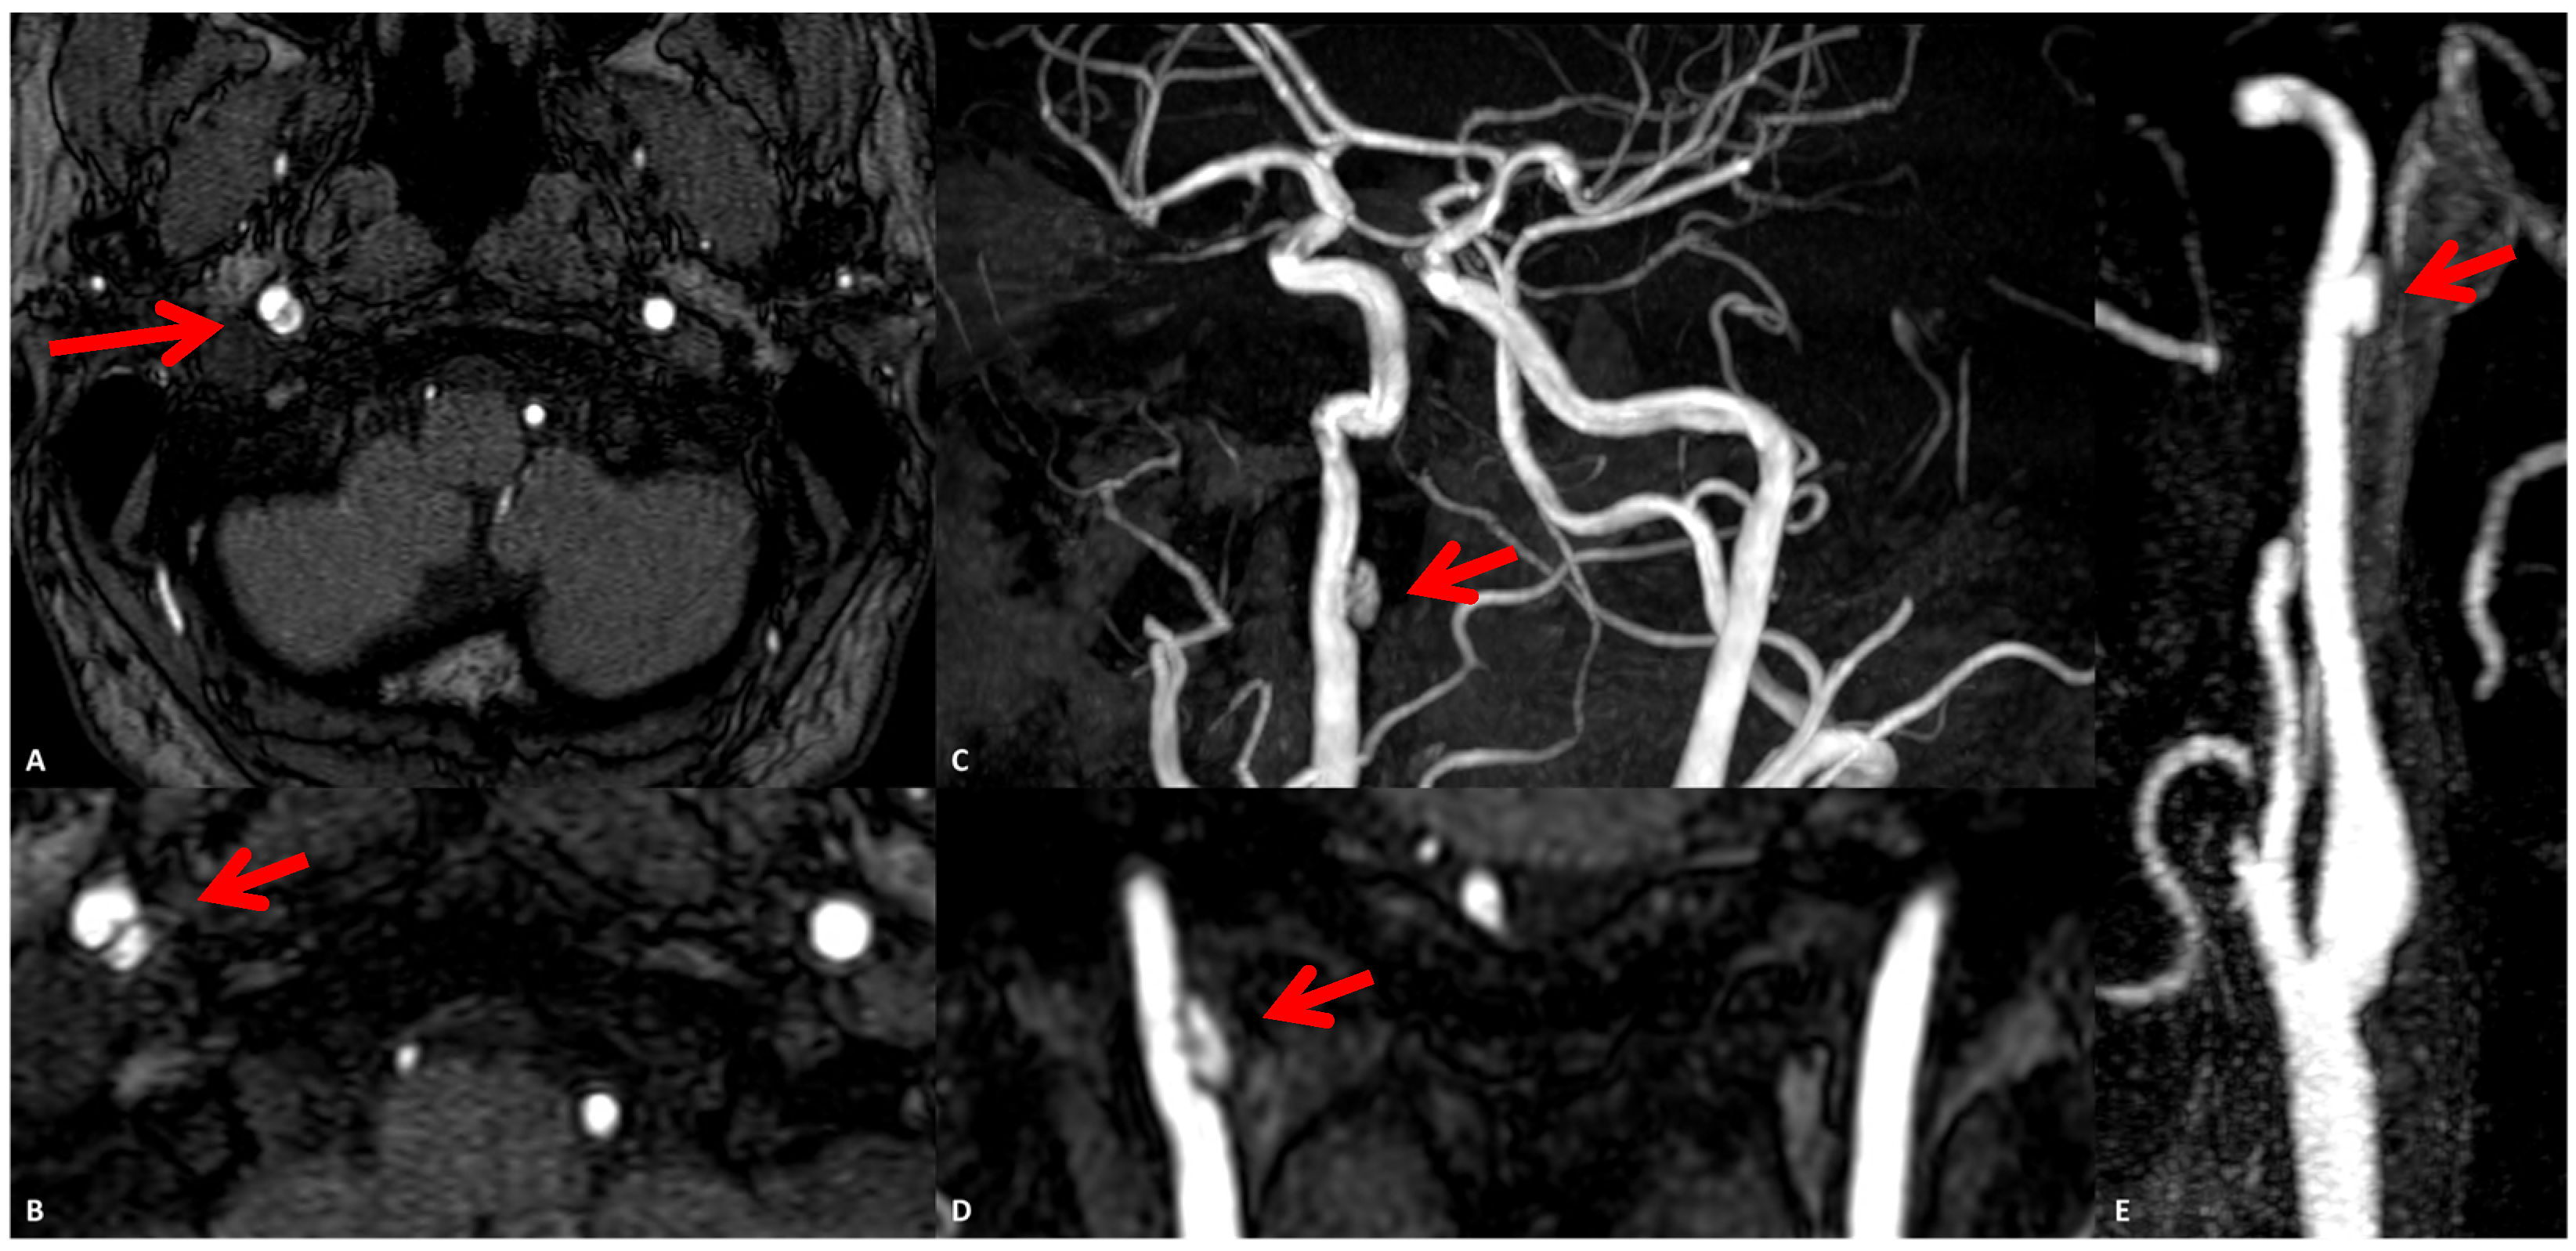

3.1. Case 1